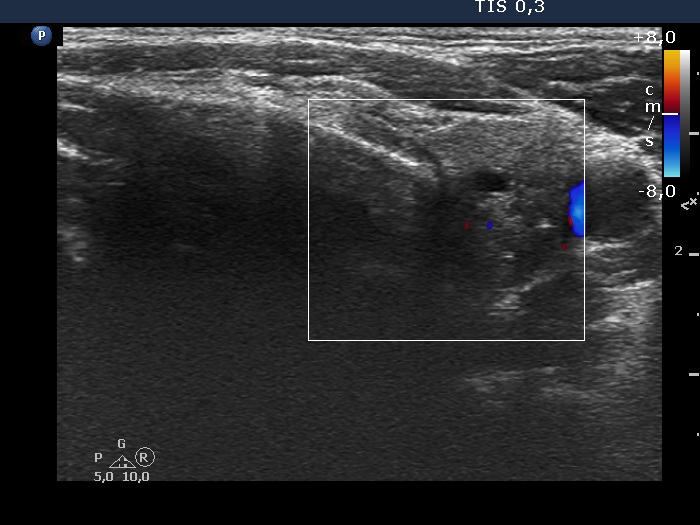

Left lobe, transverse scan, color Doppler mode. The vascularization is scanty.